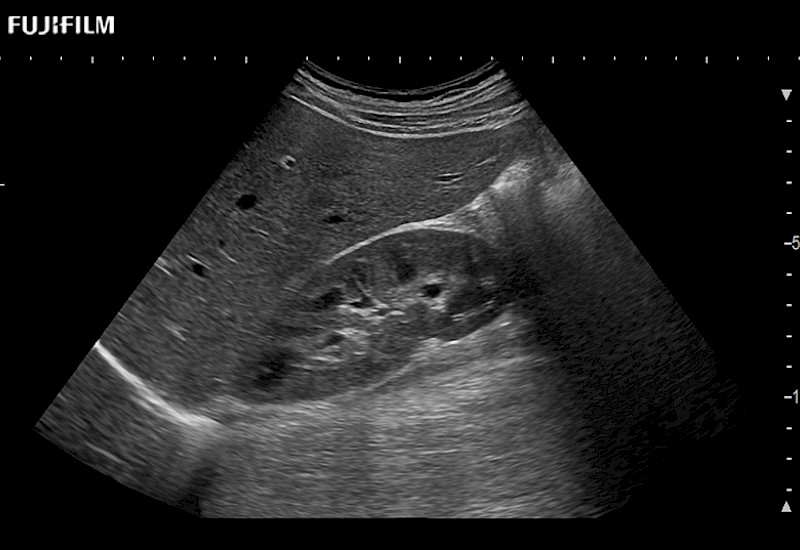

Extraordinary high-resolution digital imaging

Multi-Parametric imaging modalities

- Instant feedback on tumor margin delineation

- Instant feedback on tumor margin delineation

- Instant feedback on tumor margin delineation